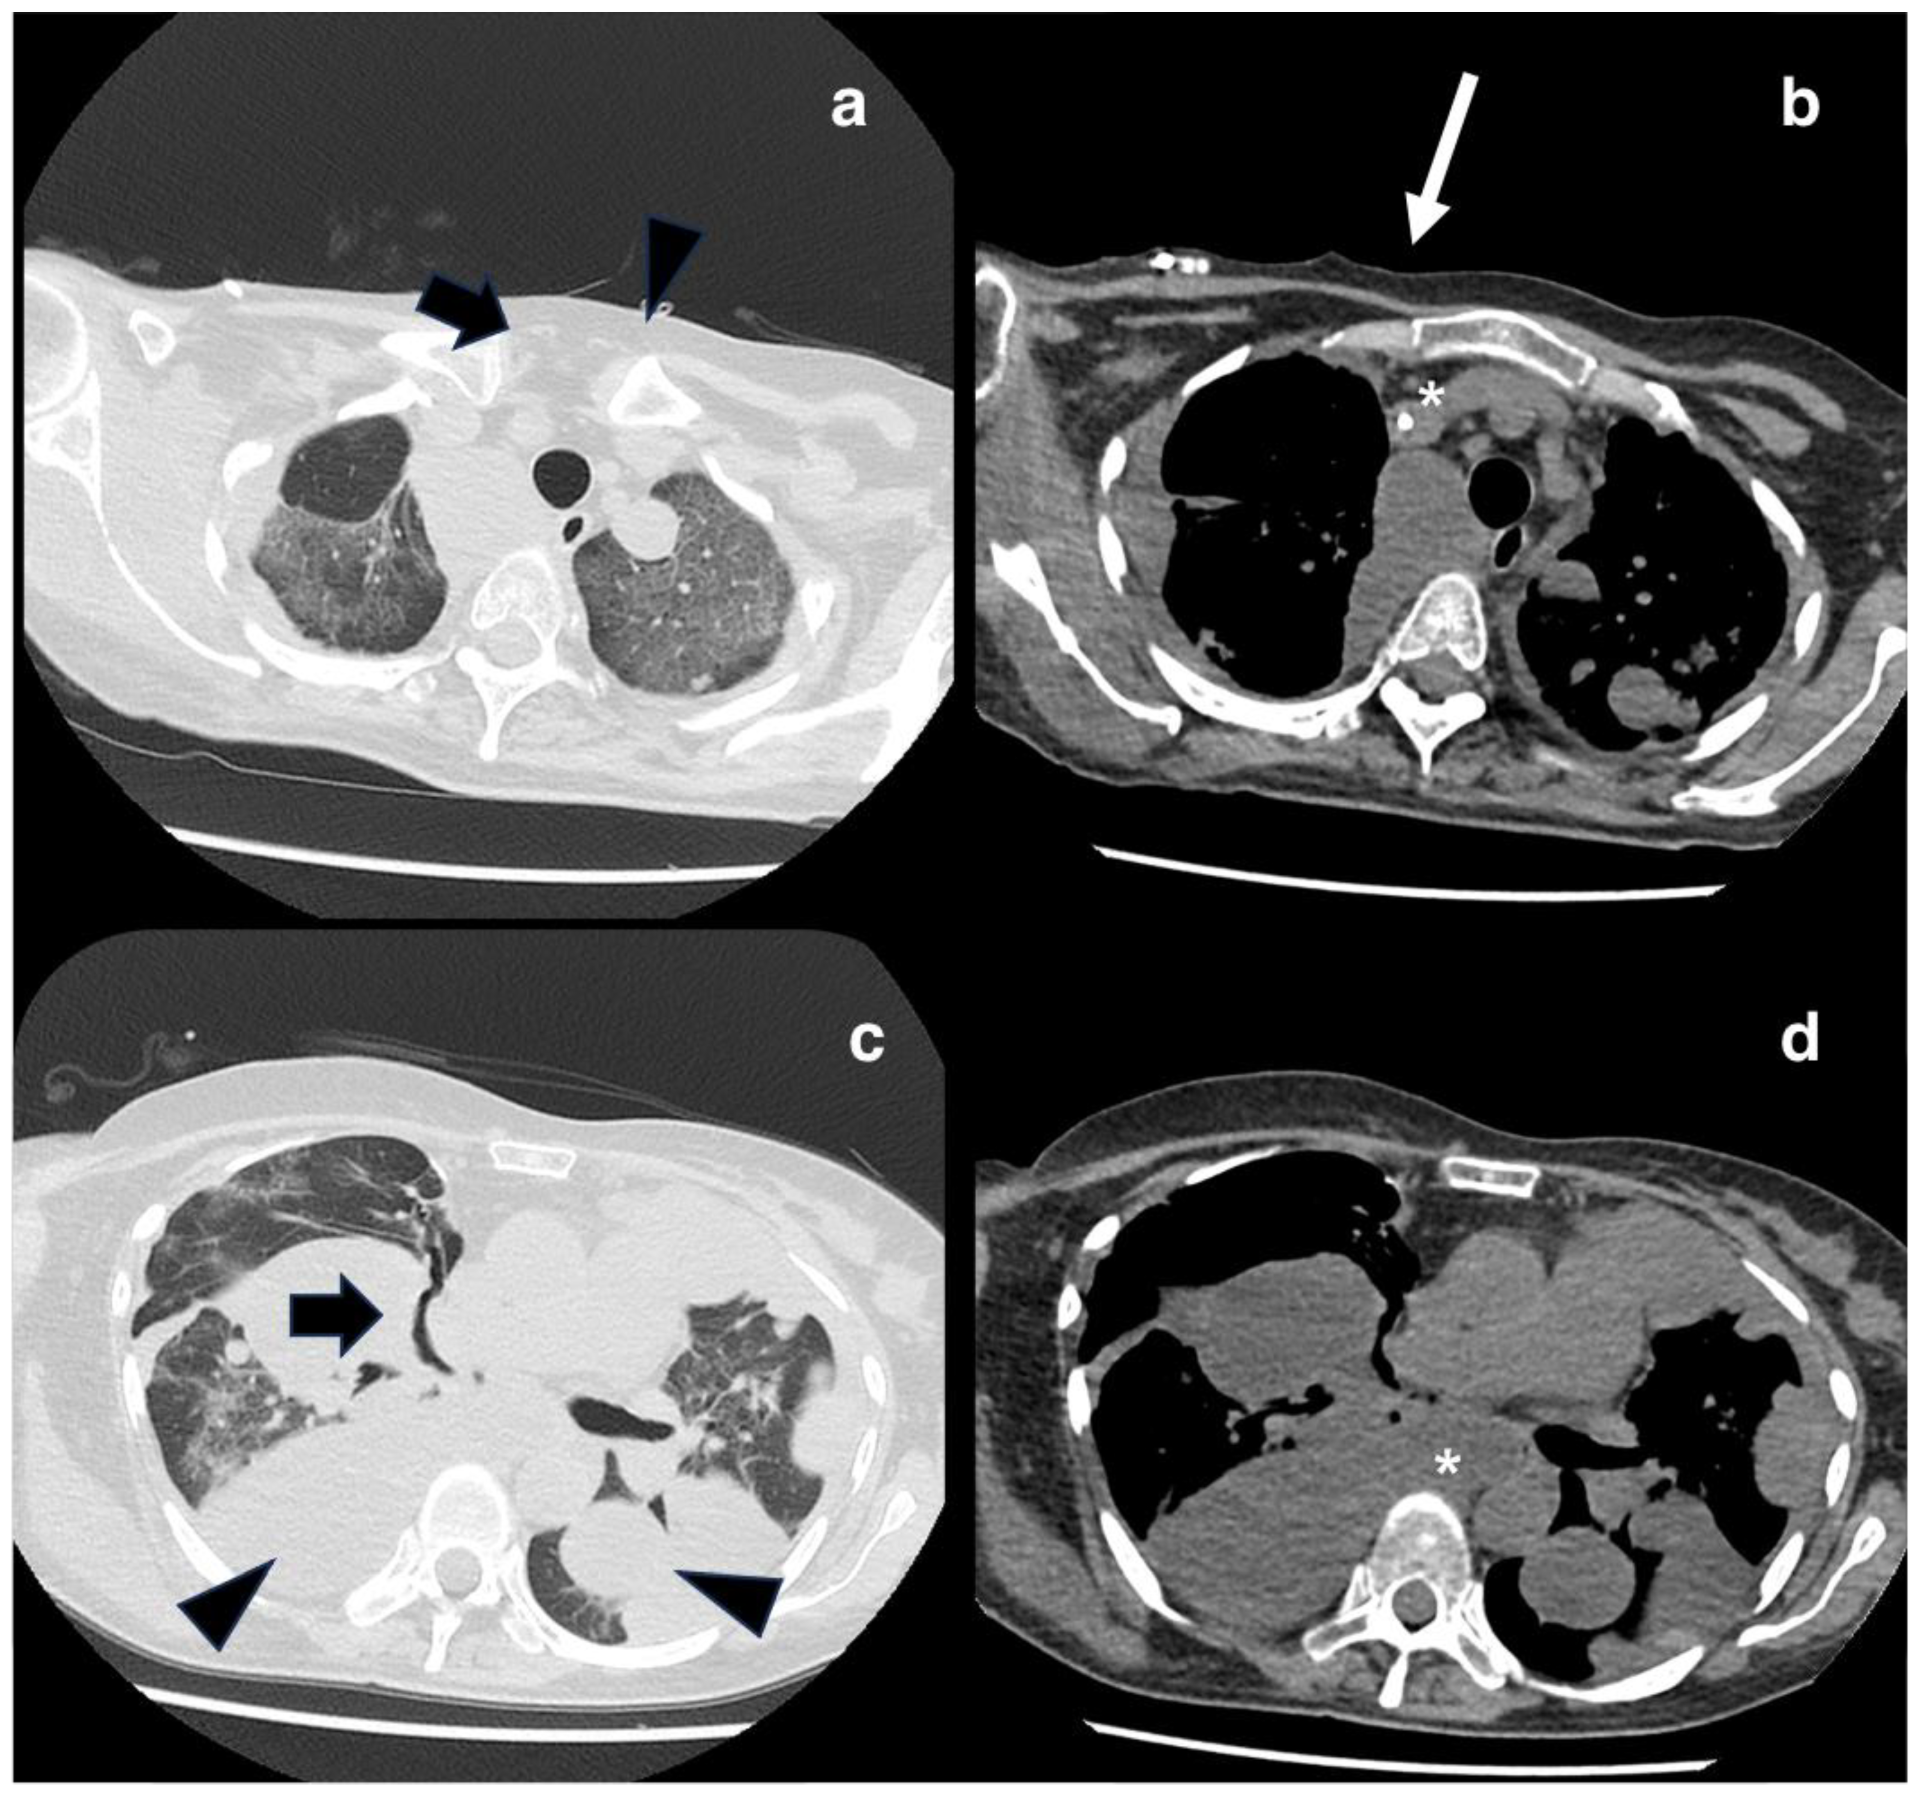

2. Case Presentation